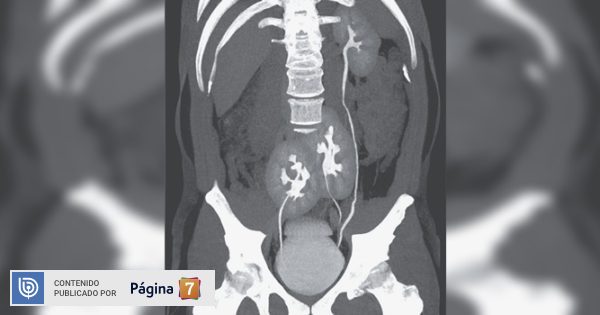

Fue la revista académica New England Journal of Medicine la que dio a conocer que la tomografía del paciente reveló que tenía tres riñones. El izquierdo tenía una apariencia normal, pero el derecho presentaba dos riñones fusionados.

El informe detalla que esta es una anormalidad congénita poco común, que probablemente tuvo un origen durante el desarrollo embrionario. Lo interesante, es que conocen menos de 100 casos en toda la historia.

Esto se conoce como ‘riñón supernumerario’: “Los análisis de sangre mostraron que su función renal era normal y, a excepción de una hernia discal, parecía estar bien. Su función renal era completamente normal. Se consideró suficiente investigación adicional con ultrasonido abdominal y tomografía ya que la causa del dolor ya había sido diagnosticada y no había otros cambios en las pruebas de laboratorio”.